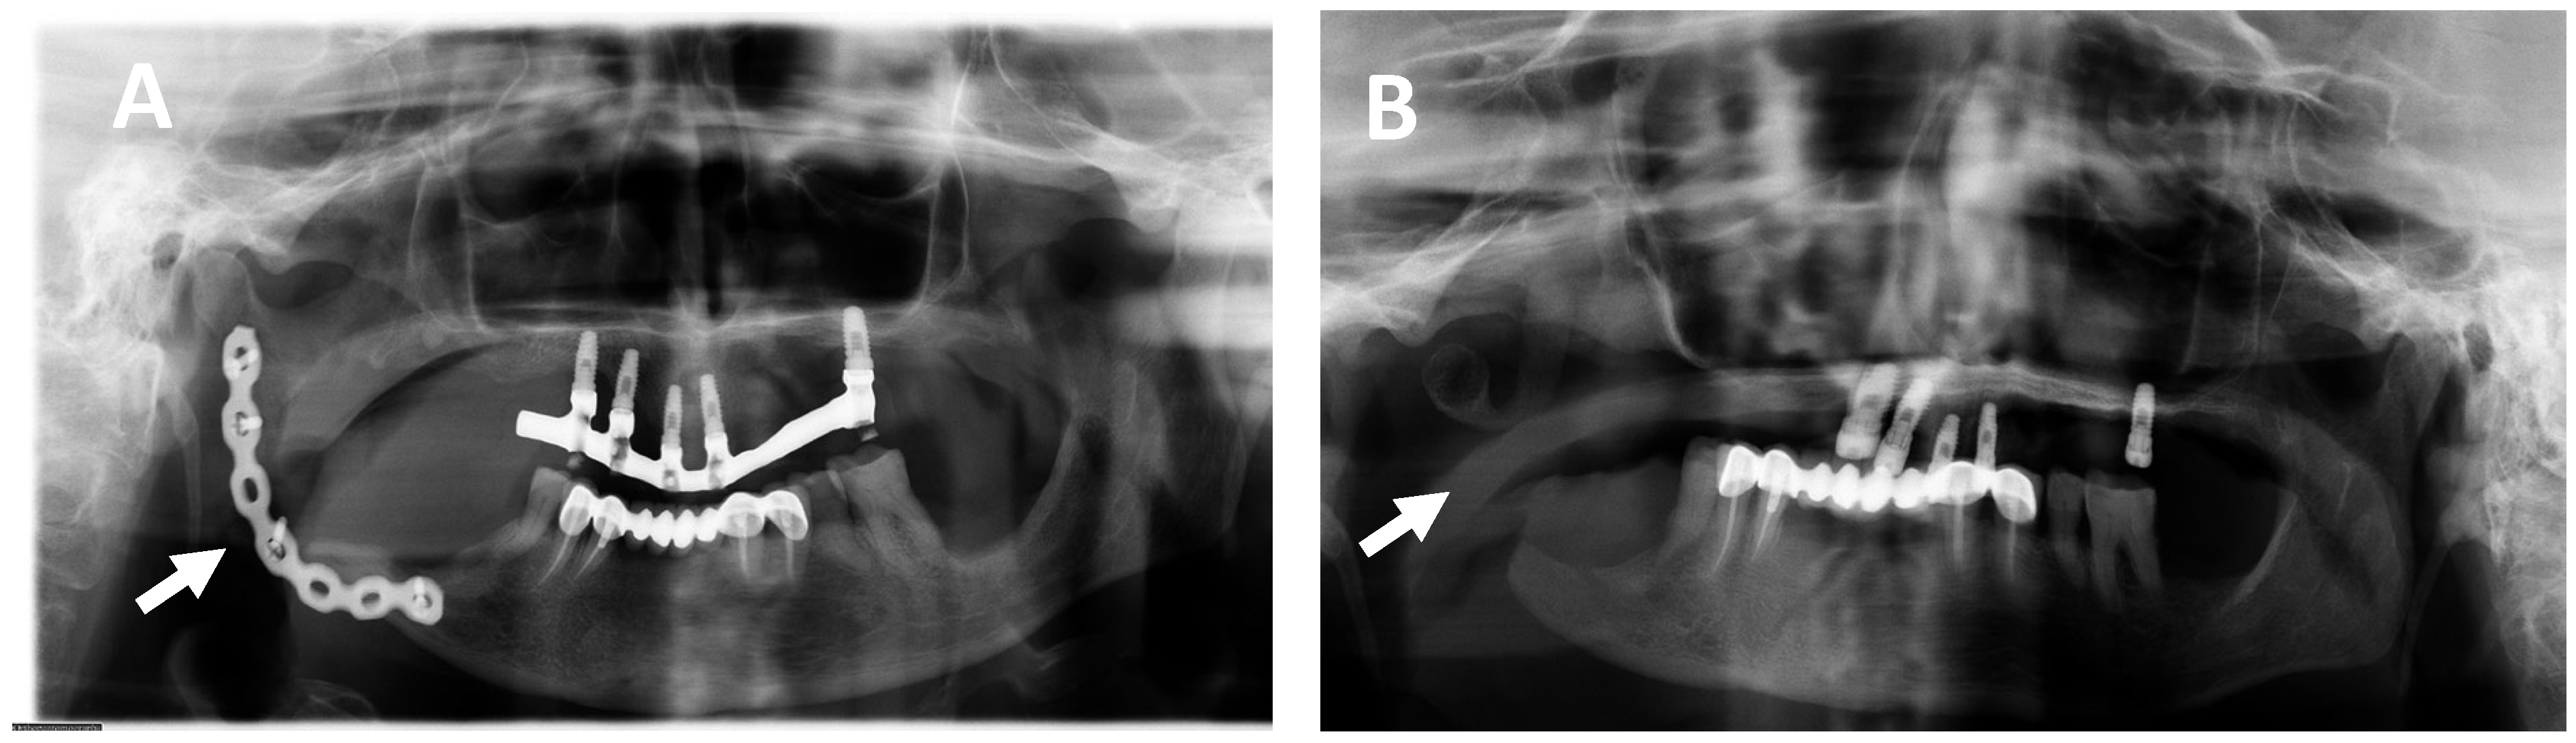

2.1. Clinical and Histological Manifestations of the Tumors

4.2. Magnetic Resonance Imaging